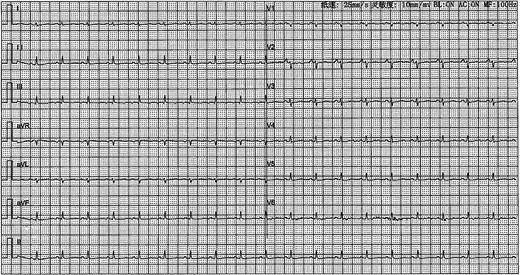

A 41-year-old female was admitted to our hospital with chest tightness and dyspnea for the past 2 weeks. Physical examination revealed bilateral lower limb edema without cardiac murmurs or jugular venous distention. Laboratory findings were notable for hypoalbuminemia (30 g/L) and an elevated D-dimer level (6.99 mg/mL), without remarkable blood routine examination and serum chemistry. Electrocardiography demonstrated sinus tachycardia and low-voltage complexes (Fig. 1). Echocardiography identified a large, well-demarcated hypoechoic mass (82 × 54 × 58 mm), nearly occupying the entire right atrial cavity (Fig. 2a and b). Contrast-enhanced computed tomography confirmed right pleural effusion and a right atrial occupying lesion (Fig. c and d). Subsequent right thoracentesis revealed exudative fluid with no evidence of malignancy on cytological examination. Further metabolic imaging with PET-CT (Fig. 3a and b) and PET-MR (Fig. 3c and d) demonstrated a hypermetabolic soft tissue mass within the right atrium, highly suggestive of primary cardiac angiosarcoma, with no signs of distant metastasis.

Electrocardiography demonstrated sinus tachycardia and low-voltage complexes.